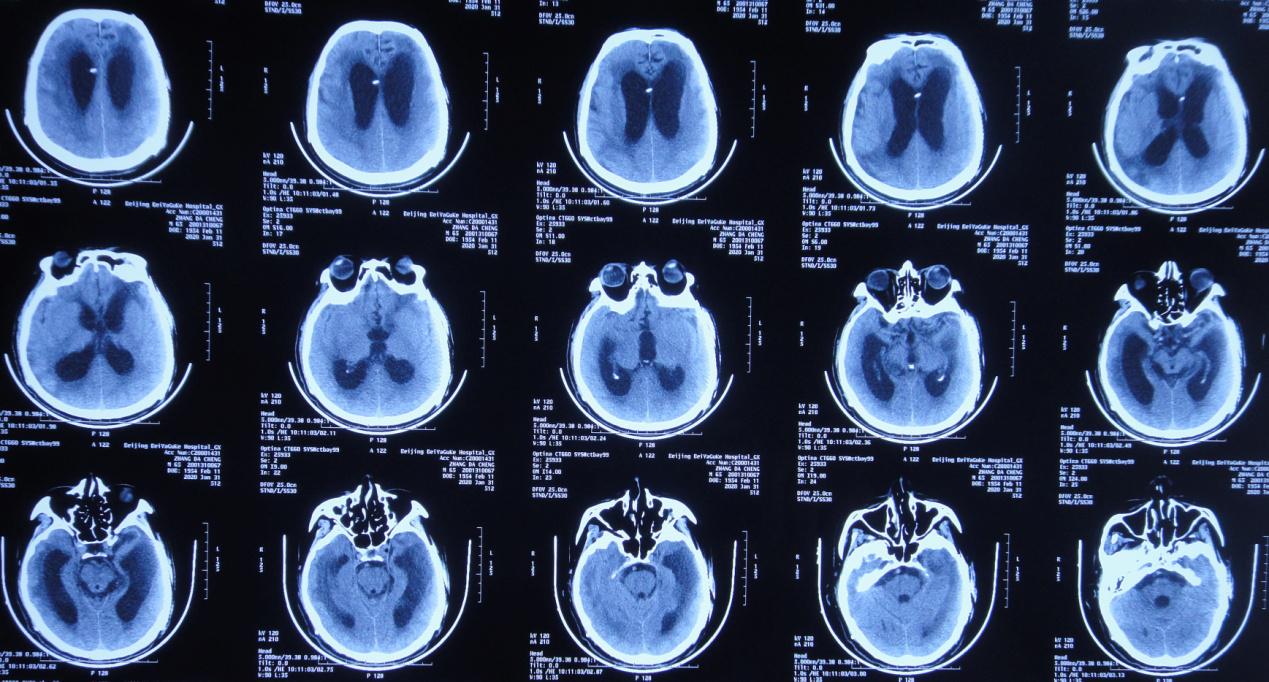

左颞叶血肿清除+去骨瓣减压术后第45天,即2019年8月24日,复查头颅CT( 图-3 )示颅脑术后改变,脑室基本“正常”,脑室周围稍水肿。

图-3: 2019年8月24日头颅CT

左颞叶血肿清除+去骨瓣减压术后第52天,即2019年8月31日,复查头颅CT( 图-4 )示脑室较前无明显变化,脑室周围仍稍水肿。

图-4: 2019年8月31日头颅CT

左颞叶血肿清除+去骨瓣减压术后第63天,即2019年9月11日患者言语较前清晰,单侧搀扶下可行走,复查头颅CT( 图-5 )(双颞增大)脑室较前仍无明显变化,但脑室周围水肿稍加重。

图-5: 2019年9月11日头颅CT

左颞叶血肿清除+去骨瓣减压术后第99天,即2019年10月17日患者言语基本清晰,可独立缓慢行走,复查头颅CT( 图-6 )示:颅脑术后改变,脑室较前无变化,脑室周围水肿较前无变化。

图-6: 2019年10月17日头颅CT